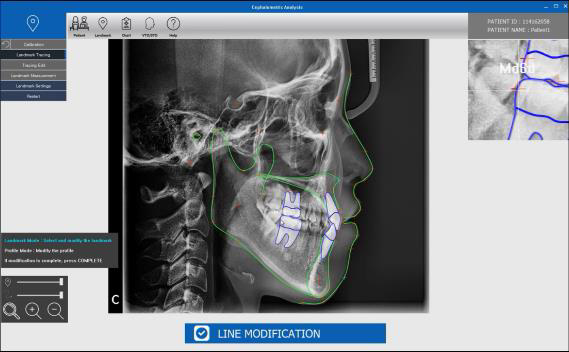

自動Ceph分析軟體